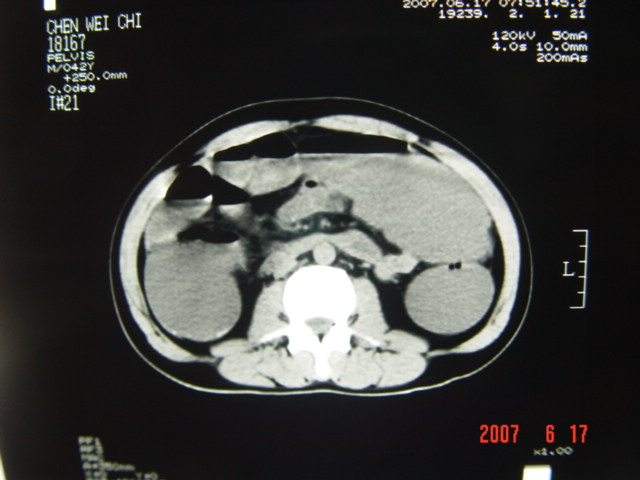

[br][br]以下是引用lkc8963在2007-6-17 13:32:00的发言:[br]完全支持邓主任意见:降/乙交界部占位性病变伴不全梗阻.做个增强或者be可能更好.